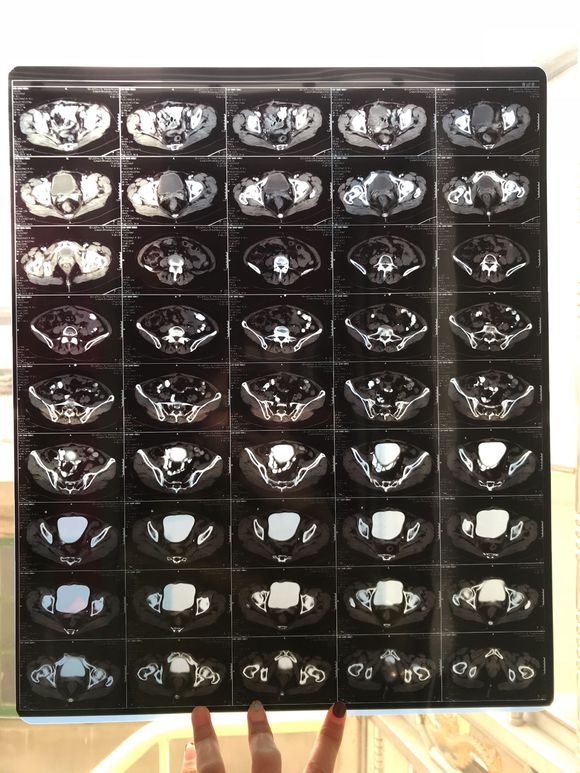

和你的故事 02019-04-09 患者家属我妈妈的病理结果报告,3期c1,大家可以帮忙看看吗,跪求了!我很急,谢谢!想知道是否严重,目前等术后出院后去肿瘤医院...

0人关注 4个回复 3522次浏览 -